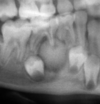

- scalloped margins with soup bubble appearance

- displaces and resorbs roots

- right angled trabecular

Radiographically: radioopaque mass fused to root with radiolucent halo present. Root resorption and fusion